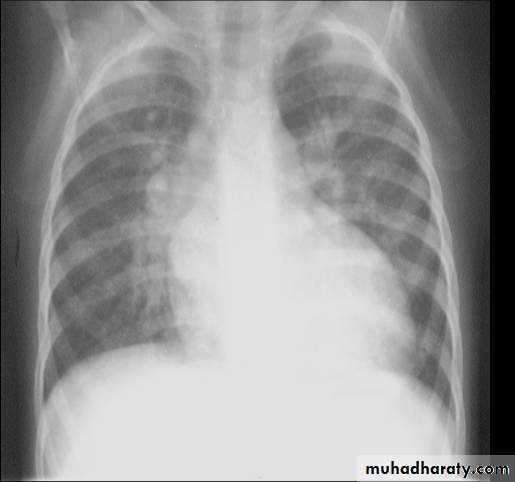

• X-ray findings• small VSD normal

• large VSD cardiomegaly, dilated pulmonary vessels (plethoric lung)

1. LV and RV enlargement with Left ventricular type

2. Pulmonary vasculature is increased.

3. Prominent PA segment

4. Normal or smaller aorta